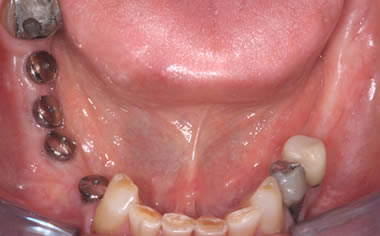

More back teeth replaced by dental implants

Case Four (4 images)